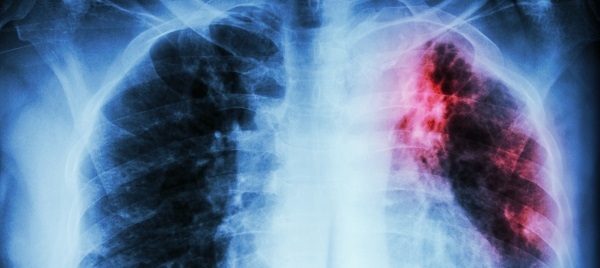

No ano passado, o Brasil registrou 66.819 ocorrências novas de tuberculose, com um coeficiente de incidência de 31,6 casos por 100 mil habitantes. A infecção, que afeta principalmente os pulmões, deixa o estado brasileiro entre os 30 países de alta carga para a doença bacteriana. Os dados são do boletim epidemiológico da Secretaria de Vigilância em Saúde do Ministério da Saúde, divulgados neste mês de março de 2021.

Embora tenha sido observada uma constante queda entre 2011 e 2016, houve um aumento importante no coeficiente de incidência entre os anos de 2017 e 2019. Em relação ao sexo, foram registrados 46.130 (69%) casos em homens, com maior prevalência em etnia preta/parda, com variação de 60,2%.